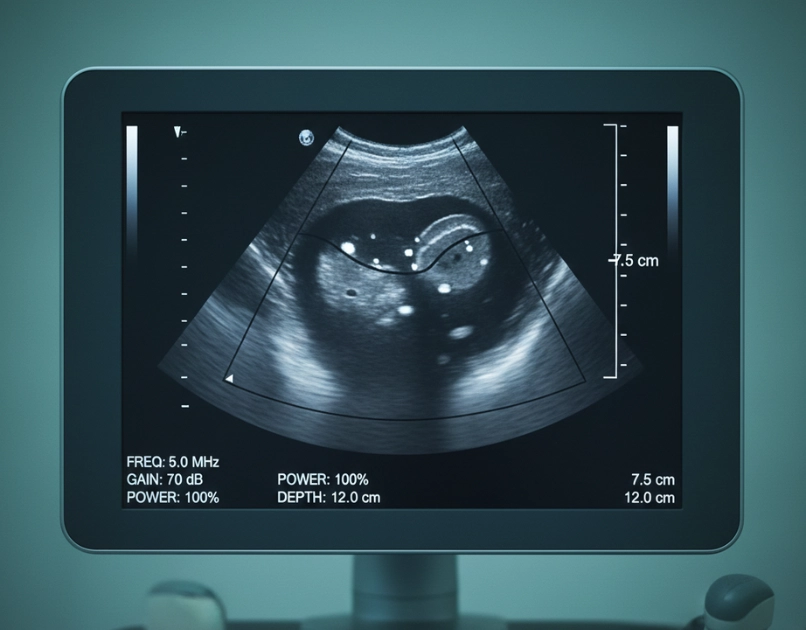

Diagnosis includes ultrasound to confirm gestational age, pelvic examination, and blood tests to evaluate overall health. Doctors check for infections, measure hemoglobin levels, and assess Rh factor before planning the procedure. A detailed medical history is reviewed to ensure the procedure is safe and appropriate for the patient. Diagnostic steps help determine the correct D&E approach.